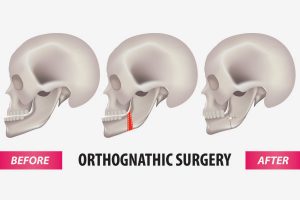

Types Of Surgical Orthodontics (Orthognathic Surgery)

www.melbourneorthodontics.comOrthognathics In San Antonio, TX - Advanced Oral Surgery

www.melbourneorthodontics.comOrthognathics In San Antonio, TX - Advanced Oral Surgery